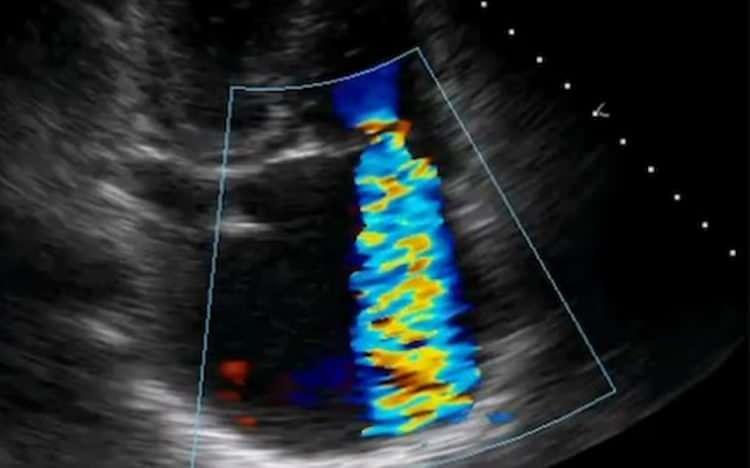

Almanya'nın konuştuğu Türk doktor: Kalp ameliyatında devrim gerçekleştirdi

Ardından bu yeni yöntemin diğer hastalarda da başarıyla uygulanmaya başlandığını ve dünyada bu yöntemle tedavi edilen hasta sayısının 80 olduğunu kaydeden İnce, "Almanya'da bu araştırma bakımından ilk 3 hasta bizim merkezlerimizde tedavi oldu. Hastalar çok iyi gelişme gösterdi." dedi.